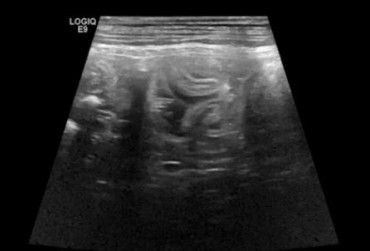

Torbiel pierwotna jest rzadką wadą rozwojową występującą u człowieka, psa, kota i konia. W niniejszym artykule opisano przypadek torbieli pierwotnej jelita prostego u dziewięcioletniego kota rasy Manx, u którego występowały przewlekłe zatwardzenia. W badaniu rektalnym i radiograficznie stwierdzono obecność miękkiego guza dogrzbietowo i bocznie od jelita grubego. Badaniem ultrasonograficznym i w tomografii komputerowej uwidoczniono dobrze odgraniczoną, cienkościenną torbiel, częściowo zamykającą światło kanału miednicy. Torbiel usunięto chirurgicznie z dojścia okołoodbytowego. Nie stwierdzono połączenia torbieli ze ścianą prostnicy. Badanie histopatologiczne potwierdziło postawione podejrzenie torbieli pierwotnej. Po wykonanym zabiegu objawy kliniczne całkowicie ustąpiły.